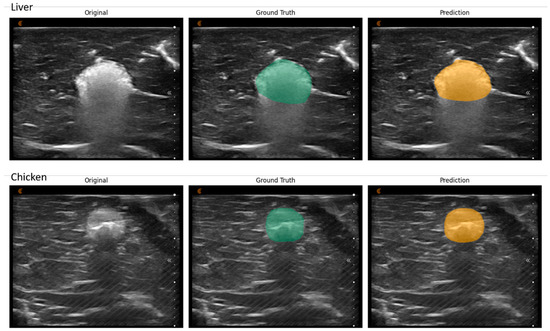

Notably, the AZ in chicken breast tissue appeared less hyperechoic in US images compared to liver tissue, as depicted in Figure 2. Conversely, the growth of the AZ around the RFA probe was shaped as an oval in chicken breast tissue, whereas, in liver tissue, the AZ assumed a more elliptical shape. As RFA progressed, increased image artifacts arose due to tissue heating and the forming of gas bubbles, thus creating a posterior shadowing effect, and complicating the assessment of the lower AZ contour. Figure 2 illustrates examples of these image artifacts.

Figure 2.

Representation of AZ in US images of liver (first row) and chicken tissue (second row) and the labelled mask (green) and predicted mask (orange). The AZ is less hyperechoic represented in chicken breast tissue as in liver tissue. Larger image artifacts can be observed underneath the AZ in liver tissue with ongoing RFA, making the assessment of the under AZ contour difficult. An acoustic shadow can be observed in the case of chicken breast.

When examining AI’s performance relative to manual measurements, it was noted that AI more accurately delineated the AZ in chicken breast tissue compared to liver tissue (Figure 2). This discrepancy may be attributed to the differential impact of US image artifacts on tissue visibility, with chicken breast tissue presenting fewer disturbances. This observation is supported by comparisons with existing literature, where AI’s efficacy in AZ detection showcases the potential for more accurate assessments in conditions with less ultrasonic interference [46]. The challenges associated with ultrasound image artifacts, such as shadowing and speckle noise, were minimized by allowing the model to learn the representation of such artifacts during the training process. As the model was trained with the expert’s labels, it behaves in a similar fashion regarding the AZ.